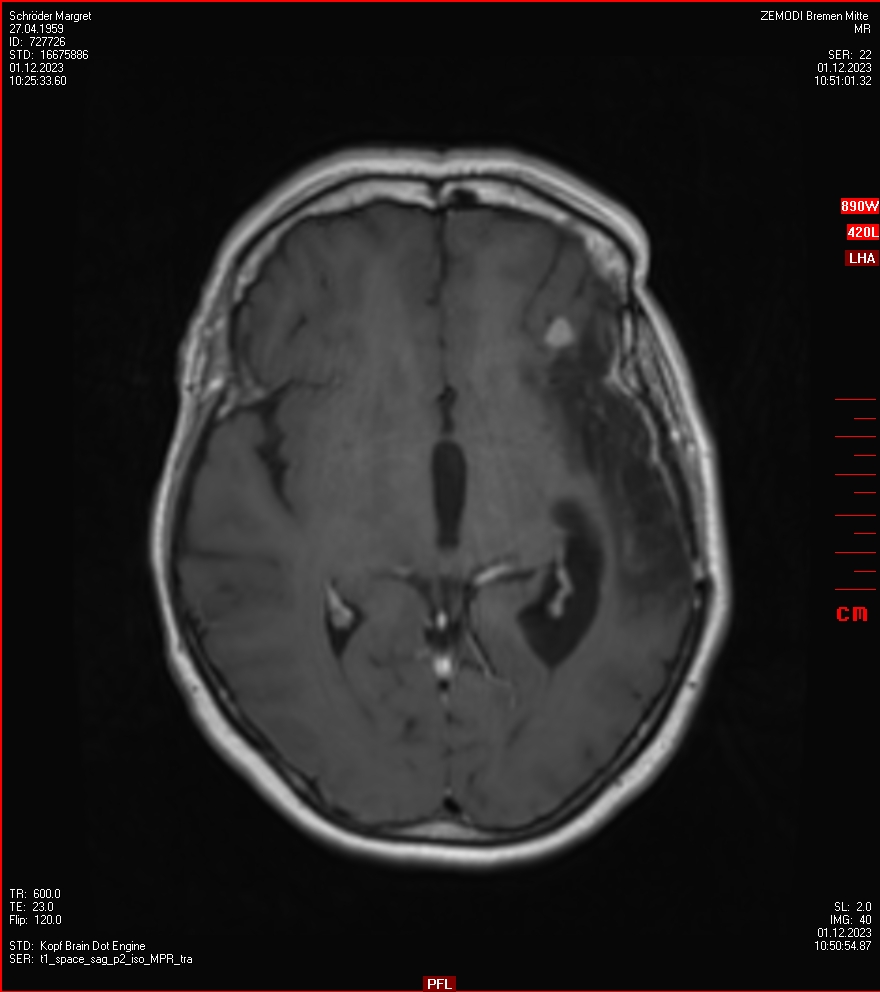

Zum Vergleich nun auch die Bilder vom 1.12.2023:

Ich denke, in den letzen 12 Monaten sind da ein paar Rezidive gewachsen,  vor 12 Monaten waren sie auch schon zu erkennen - vorher noch nicht. Nun hoffe ich auf den Rat des Spezialisten. Hoffendlich kann man etwas machen.